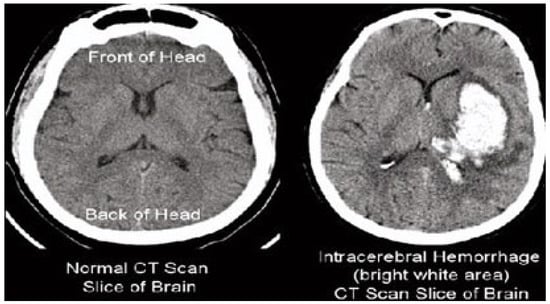

The results of the steganography technique are shown in Figure 2; the changes in both the cover image and the steganography image cannot be distinguished. This demonstrates the superiority of the LSB replacement method in the field of steganography. The resulting steganography image is then transformed to render the image unreadable, and compression techniques are used to store the medical image in a database properly. This scenario is illustrated in Figure 3. This diagram shows the order of conversion, compression, decompression, and inverse conversion processes. To realize this methodology, we took as input cerebral hemorrhage steganography images already embedded in patient data and applied the DWT to obtain the transformed images.

Figure 3.

Hybrid transformation and compression.

The “dwt2” method is used for the conversion. In the DWT process, the original image is decomposed into up to two levels using the “Haar” wavelet. This decomposition produces horizontal, vertical, diagonal, and proximity components. The decomposed components are reconstructed using the DIWT to recover the original image. This strategy is illustrated in Figure 2, and the compression method takes a decomposed image as input and compresses it using a wavelet packet compression technique using “Haar” wavelet packets. The compression method, “wpdencmp,” uses a soft thresholding technique that uses wavelet packets to compress the image and compute the threshold. This compression concept is illustrated in Figure 3, along with histograms of the original and compressed images. A step-by-step compaction process is shown in Figure 4. At each level, the images are refined, and the differences between levels are visible. The higher the number of coding levels of compression, the higher the image’s compression ratio and recovered energy. The compressed image is decompressed by wavelet packet reconstruction using the accounting matrix values of the decomposed image. Horizontal, vertical, diagonal, and proximity components are extracted from the decompressed image, and an IDWT is applied to recover the original image. A title image embedded in the patient data is visualized.

In Figure 3, the steganography image of the brain hemorrhage is taken, and DWT is applied. After compression, the compressed image is displayed as a bar graph. The wavelet reconstruction method recovers the compressed image from the compressed image. The target image is retrieved from the decompressed image by applying the IDWT method to the previous step. Figure 4 represents the DWT and IDWT of the brain hemorrhage image. A sample segmentation of the transformed image is also displayed.